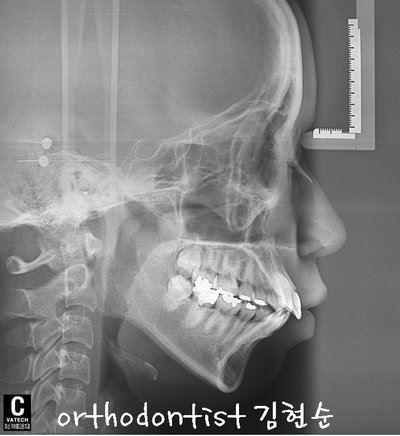

Chief Complaint

Treatment plan.